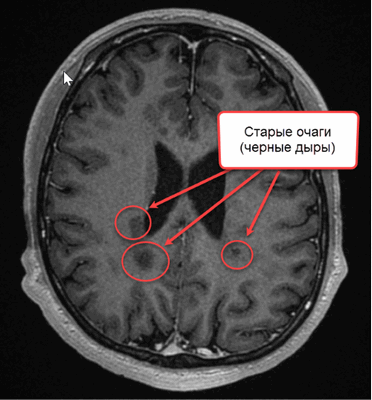

Конечным этапом прогрессирования поражения при рассеянном склерозе являются “черные дыры”, свидетельствующие о деструкции аксонов.

На МР-томограмме головного мозга в Т1 ВИ можно увидеть многолетние очаги РС (обозначены стрелками)